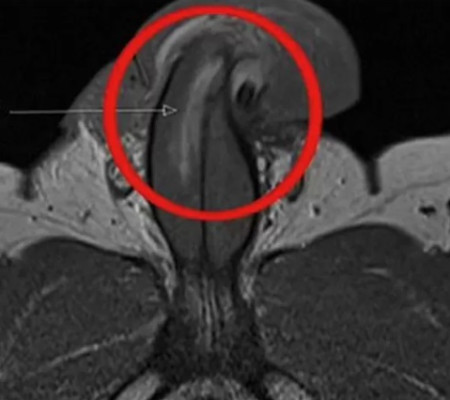

Imagem revela ruptura vertical (British Medical Journal)

No entanto, no caso do homem cujo pênis foi fraturado verticalmente, os médicos disseram que ele não relatou nenhuma sensação de estalo, perda gradual da ereção ou inchaço moderado. Após uma ressonância magnética, um cirurgião confirmou que ele sofreu uma ruptura vertical de três centímetros no pênis.